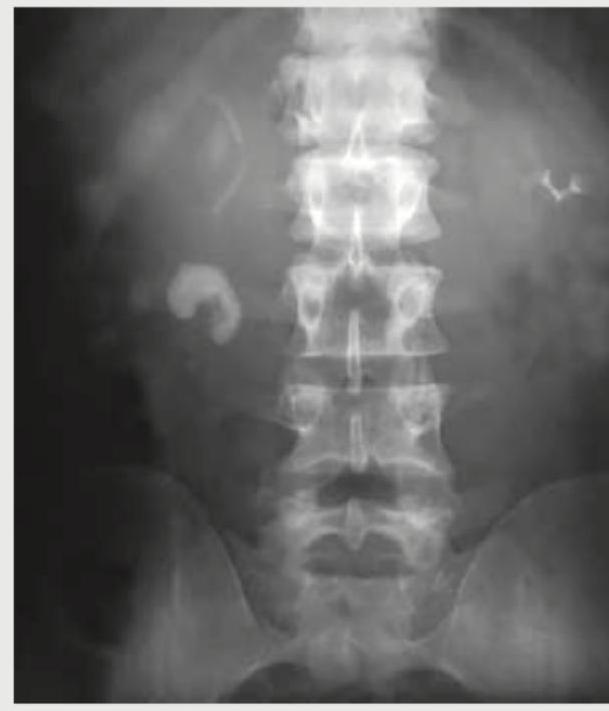

A 26-year-old construction worker with a previous history of recurrent kidney stones presents with flank pain. What is the radiological sign demonstrated in the IVP image shown below?

Explanation: ***Rim sign*** - The image shows a **calcified rim around a radiolucent (non-calcified) center**, which is characteristic of a **calcium oxalate monohydrate stone** on an intravenous pyelogram (IVP). - This sign is also known as the **"lucent-centered calculus"** or **"target sign"** and indicates a partially calcified stone. *Ring sign* - The **ring sign** can refer to various appearances in medical imaging, often indicating a **ring-enhancing lesion** on CT or MRI, which is not applicable to a kidney stone on IVP. - In renal imaging, a ring sign might describe a collection of contrast medium around a tumor or cyst, but not typically a stone with a radiolucent center. *Egg in cup appearance* - This sign is typically associated with **osteochondroma or enchondroma** lesions in bone imaging, where the cartilage cap creates a "cup" for the medullary bone to grow into. - It is not a recognized sign for kidney stones. *Sun burst appearance* - The **sun burst appearance** is characteristic of certain **bone tumors**, particularly **osteosarcoma**, where new bone forms perpendicular to the bone surface. - This description does not apply to the radiological features of kidney stones on IVP.